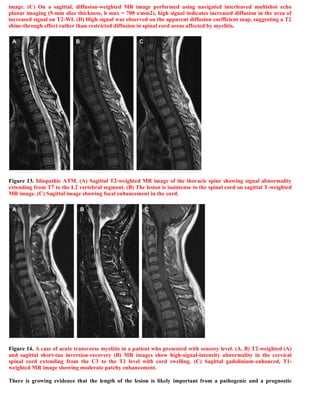

This document discusses a case of spinal multiple sclerosis in a 40-year-old patient. MRI images show well-defined pencil-shaped lesions occupying 2-3 spinal segments that are hypointense on T1-weighted images and hyperintense on T2-weighted images. Diffuse abnormalities are also seen as poorly demarcated hyperintense regions on T2-weighted images. The diagnosis is spinal multiple sclerosis. The document then discusses features of spinal MS lesions seen on MRI such as focal lesions, diffuse abnormalities, and spinal cord atrophy, and compares features of MS to other conditions like neuromyelitis optica.